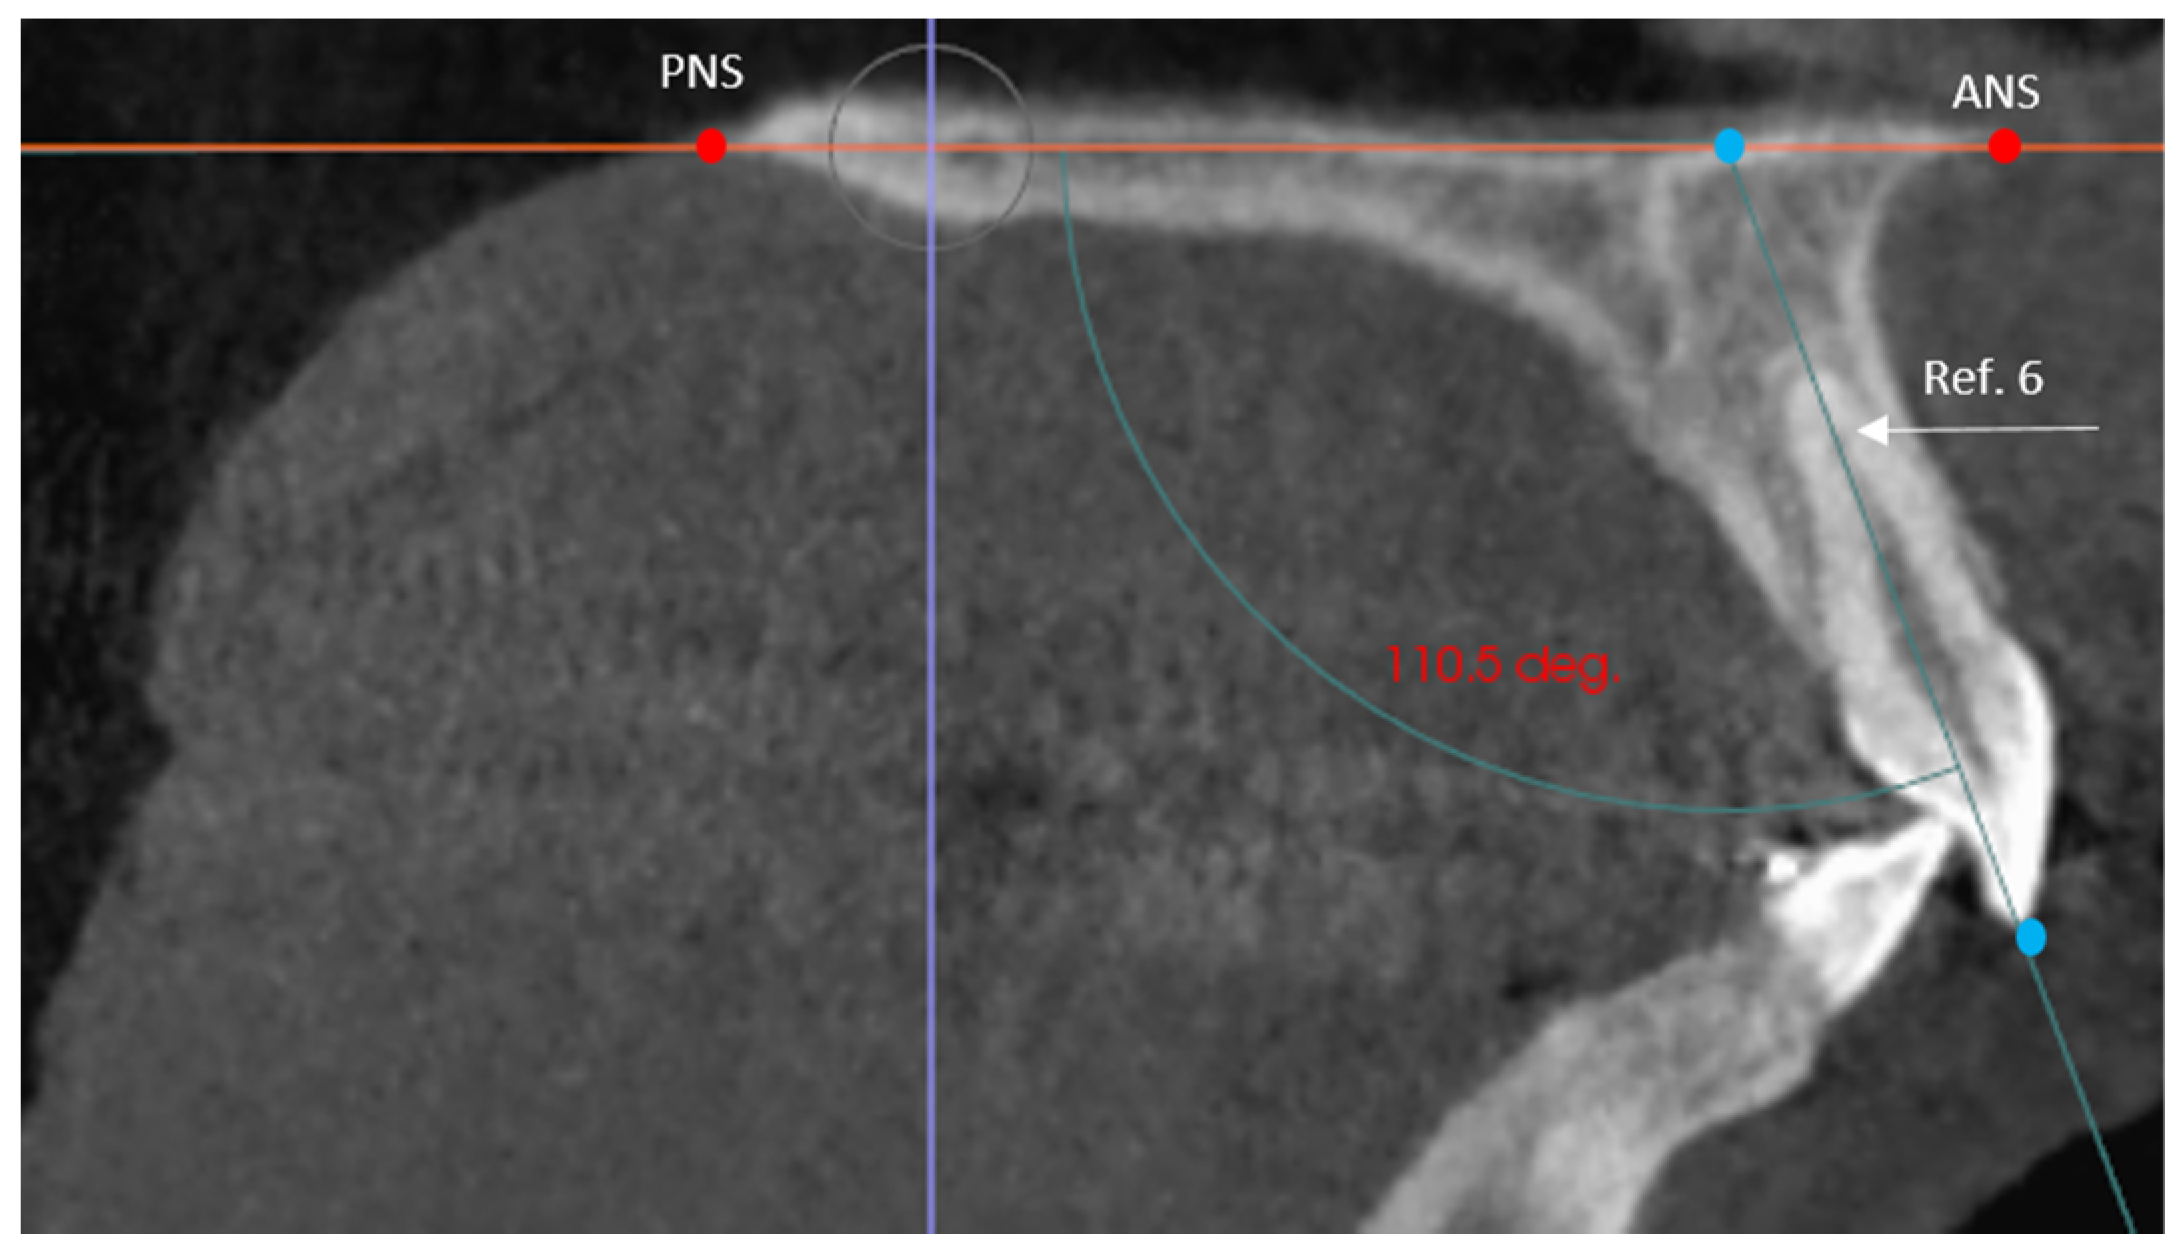

- The angle of the coronal inclination of the upper right and left central incisors with respect to the palatal plane (II) was measured in the sagittal plane (anterior nasal spine-posterior nasal spine) [33] where the angle obtained is that between the major axis of the upper incisor and the palatal plane in the GI and GC. In the GI-R and GI-L subgroups, the coronal inclination of the upper right and left central incisors was measured separately with respect to the palatal plane (II′) (Figure 3).